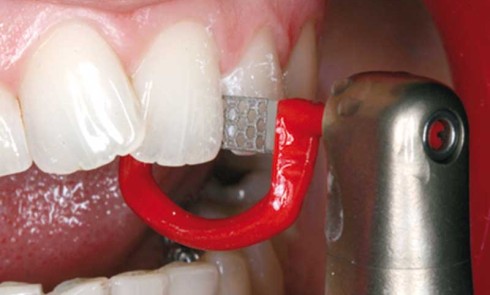

Article réservé à nos abonnés Dossier Céramique

Sommaire Les matériaux céramiques, que faut-il en retenir ? Anthony Atlan Principes des préparations antérieures pour systèmes tout céramique Jean-Philippe Pia,...